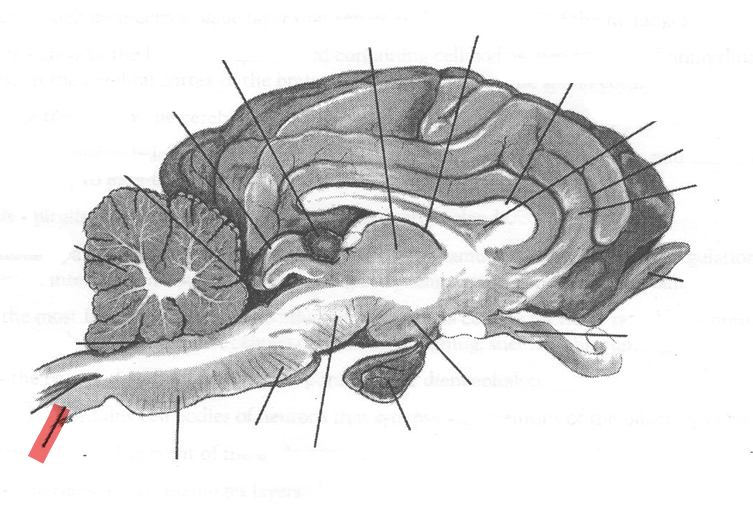

Identify highlighted arrow

Spinal cord